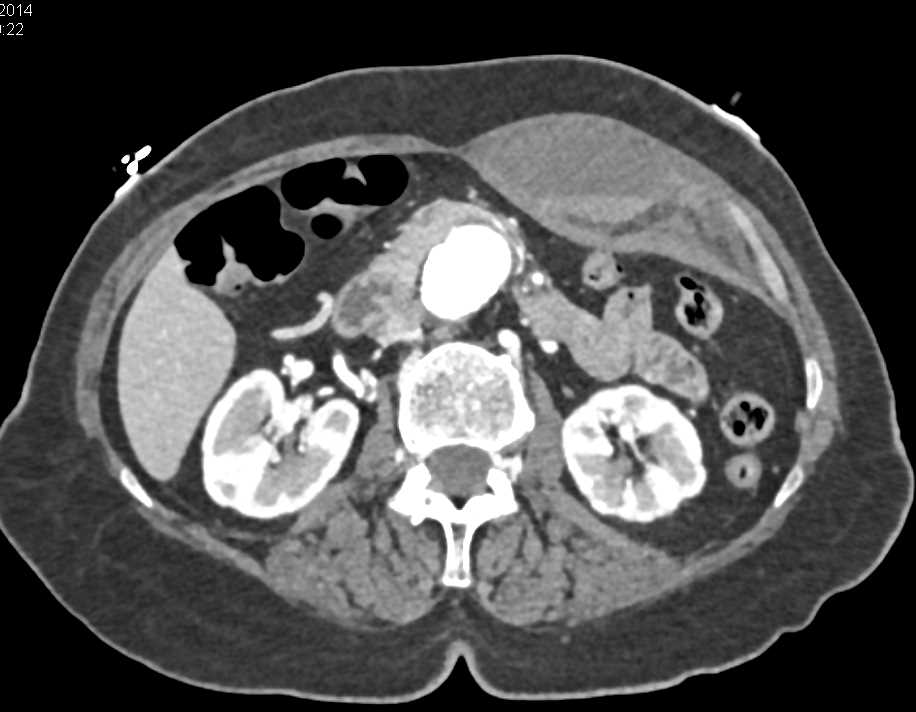

Diagnosis

Fracture Left Elbow with Poor Healing and Alignment